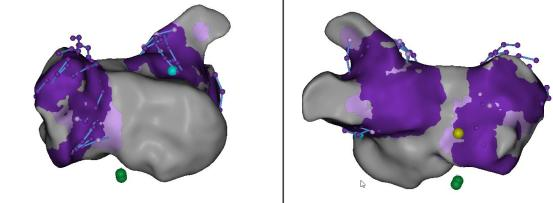

三维评判损伤形成区域:FAM coloring实时消融损伤显示,Grid overlap indication同步显示TPI阳性grid点。